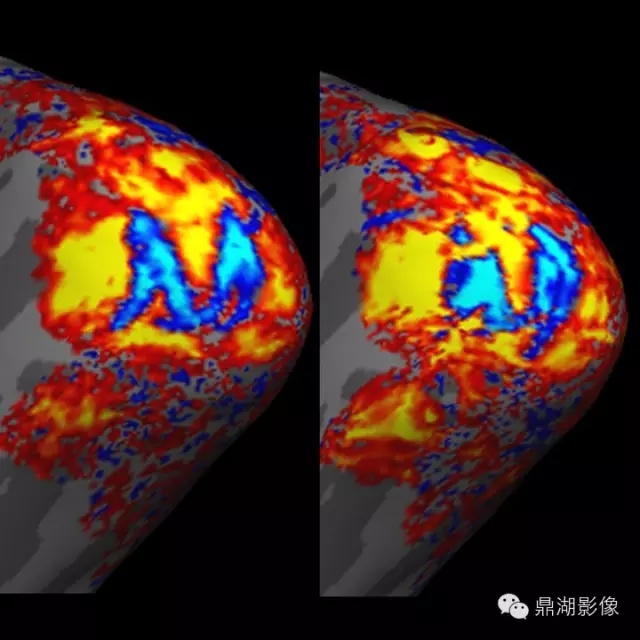

4.PET—MRI设备:PET-MRI是将PET(正电子发射计算机断层显像)的分子成像功能与 MRI (核磁共振成像)卓越的软组织对比功能结合起来的一种新技术。

一体化PET—MRI是将PET和MRI有机组合在同一个机架内,在MRI变化不大的前提下,重新设计PET探测器以适应MRI的高磁场、高射频场和高梯度切换,将PET探测器集成在MRI的射频体线圈和梯度线圈之间,一次扫描即可同时完成PET和MRI检查,可获得人体有关解剖、PET/MRI检查与其他手段相比,它的灵敏度高、准确性好,对许多疾病(尤其是肿瘤和心脑疾病)具有早期发现、早期诊断的价值。

这是一例PET-MRI诊断的盲肠炎患者,在融合后发现盲肠区域有小片状的炎症性改变,但在独立的MRI图像和FDG-PET图像上很难显示。

Images provided by Drs. Alex Guimaraes, Ciprian Catana, Bruce Rosen, and David Berger (Massachusetts General Hospital, Boston, MA).

这是一个例对灵长类动物的分子影像学研究